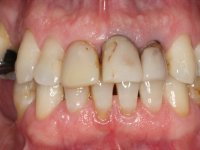

The patient had "ugly front teeth and one of them was shaking”.

Patient male, 60 years old, non-smoker. After imaging and clinical examination, it was found that the patient had teeth 2.1 and 2.2 with extensive acrylic restorations, with screwed intra radicular posts and very poor endodontic treatments. Tooth 2.2 had an extensive apical lesion, the post had been placed on a false route and had mobility. Tooth 1.1 had an extensive resine restoration and tooth 1.2 presented a mesial restoration, also in composite resin, Class III type. The antero-superior sector was vestibularized, as consequence of a loss of vertical occlusion dimension associated with posterior edentulism. The patient showed reasonable periodontal health and satisfactory oral hygiene.